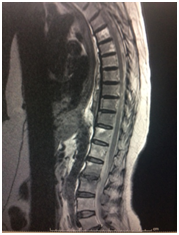

Initially ATT was started empirically along with pseudomonas sensitive antibiotics according to culture report after discussion with pathologist and microbiologist ATT Stopped and Antifungal Voriconazole 200mg started twice daily. She was responding to treatment. Her pain decreased, wound healed and no improvement in the neurology was noticed (Figure 4).

Figure 4 MRI on 01/10/2017.

She came for follow up at 6 weeks in the outpatient department symptomatically better and responding to treatment. ESR and CRP reduced marginally. Repeat blood culture showed no growth. MRI shows Multifocal involvement of lumbar and thoracic and intervertebral discs with evidence of canal stenosis and cord compression at thoracic level, no significant change compared to previous study, posterior paraspinal soft tissue with abscess formation on right side from D11-L3 level- a new development. The case was further discussed with microbiologist and infectious disease specialist at our hospital. They advised to continue the same treatment as she was symptomatically improving. But 1 month later the relatives informed us that the patient expired at home.